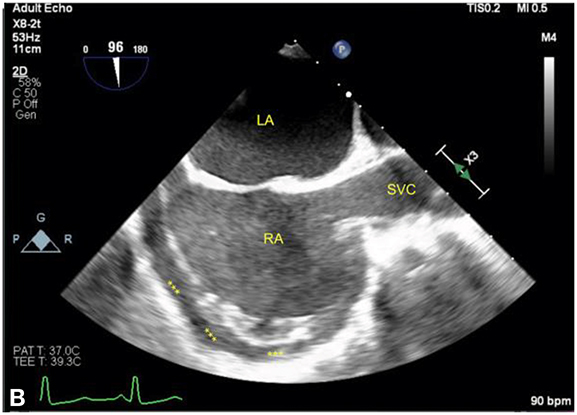

Figure 12.7.: Right Atrium (RA) Collapse from Early Cardiac Tamponade.

Right atrium (RA) collapse from early cardiac tamponade. The figures show the RA in the midesophageal bicaval view in the same patient with an acute pericardial effusion (labeled with asterisks). A. The RA is compressed by the effusion (arrows) in early ventricular systole as denoted by the ECG, corresponding approximately to the x-descent on a CVP waveform when the RA is most susceptible to compression. B. The RA in late ventricular systole is seen, corresponding to a point just before the V-wave, when the atrium is at its fullest just before tricuspid valve opening. LA, left atrium; SVC, superior vena cava.